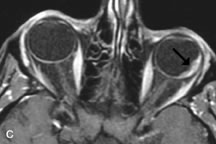

On MRI, uveal melanomas have a typical appearance that helps to differentiate them from other primary and secondary intraocular tumors as well as choroidal detachments. Pigmented melanomas are hyperintense on Tl-weighted images, hypointense on T2-weighted studies, and hyperintense on proton density–weighted examinations (Fig. 24).30,31,50,80–82 These signal characteristics have been attributed to the paramagnetic properties of melanin because of stable free radicals that shorten the T1 and T2 relaxation times. Moderate enhancement is seen on postgadolinium T2-weighted images. Gadolinium-enhanced T1-weighted images are particularly sensitive in detecting choroidal melanomas.83 MRI may be less sensitive in detecting extrascleral extension of tumor than echography performed by an experienced ultrasonographer.84

Fig. 24. A. T1- and (B) T2-weighted MR scans demonstrate a small nodular intraocular mass (arrows) that is very hyperintense on the T1-weighted scan and hypointense on the T2-weighted image. This signal intensity pattern is due to the presence of free radicals within melanin granules. C and D. Postcontrast fat-suppressed T1-weighted scans demonstrate homogeneous intense enhancement of the lesion and no evidence of seleral penetration or optic nerve invasion.